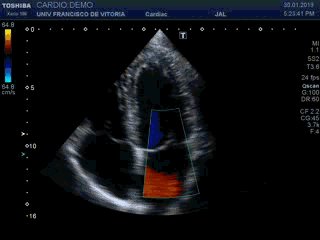

Una vez realizado el estudio 2D pasamos al estudio mediante Doppler-color. En primer lugar colocaremos una caja de color sobre la válvula mitral donde nos haremos una idea si existe regurgitación o no (insuficiencia valvular), una aceleración excesiva de la sangre en este lugar (estenosis) coincidiendo con un defecto de apertura sospechado en el 2D, o por el contrario, todo parece normal. El clip 10 muestra un llenado transmitral normal por Doppler color.

Once the 2D study was done, we went to the Doppler-color study. First we will place a colored box on the mitral valve where we will have an idea if there is regurgitation or not (valvular insufficiency), an excessive acceleration of the blood in this place (stenosis) coinciding with an opening defect suspected in the 2D, or on the contrary, everything seems normal. Clip 10 shows normal transmitral filling by color Doppler.